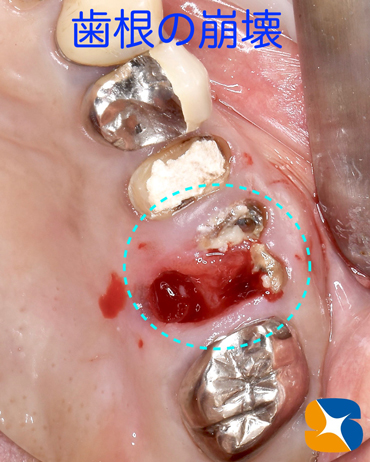

2月末。50代の女性。主訴は「奥歯がグラグラして、噛むと痛い。出血も口臭も腫れもある。口腔ガン?ではないか心配で来た。」でした。

CT撮影の結果、銀歯の根が割れていることが判明しました。歯茎の腫れを治すには抜歯の必要性があります。さらに、抜歯した後はどうされますか?

抜歯を行なったところ、2本の歯根が見事にバラバラに折れた状態で歯茎の中に突き刺さっていました。口腔ガン?と心配されていましたが問題はありませんでした。これから折れた歯根を摘出していきます。

抜いた銀歯も恐ろしい状態になっていました。